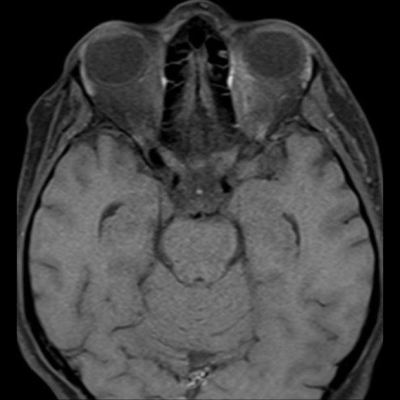

- (B) Orbita MRG’de aksiyel yağ baskılı T1A’da optik sinir prekiazmatik segmenti (oklar) gösterilmiş olup sırası ile aksiyel ve koronal post-kontrast yağ baskılı T1A görüntülerde bilateral optik sinir prekiazmatik segmentte kontrast tutulumu dikkati çekmektedir (oklar ve daire).

- Optik nörit varlığında özellikle optik kiazma ve posterior optik sinir tutulumu görülür ve bilateral olabilir.

- MOGAD hastalarında optik sinir ödemi diğer optik nörit tiplerine göre daha belirgin görülmektedir.

- MS’de optik nörit radyolojik tutulumu daha fokal iken NMO spektrum bozukluğu ve MOGAD’de genellikle daha yaygındır. MOGAD, NMO’ya kıyasla daha anterior kısmı etkileme eğilimindedir.